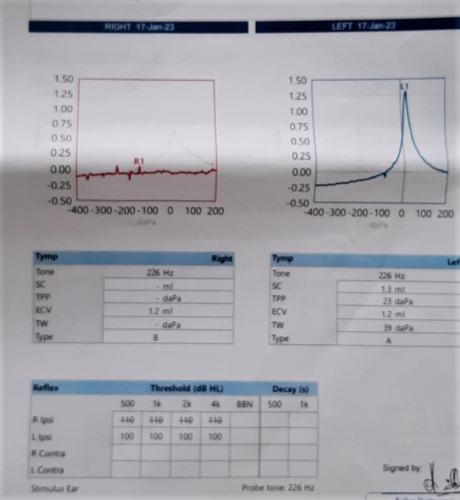

I had a hearing test which showed conductive hearing loss of about 40db around the 1k frequency range (see pictures).

The CT scan report came back saying I had Chronic Otomastoiditus and showed opacification of the Mastoid bone and middle ear space. (See pictures)

The ENT doctor thought it was chronic inflammation due to Eustachian tube dysfunction and suggested inserting a T-Tube and performing a balloon dilation, I opted out of the balloon dilation due to my occasional patulous eustachian tube (Really the ENT doctor should have flagged this up before recommending it!).

I was told that it would take a while for the middle ear inflammation to go away (6months to a year!) He also said that my right ear drum was sclerotic and rigid and my hearing would never be the same as my left ear. He said the ossicular chain (stapes,incus,malleaus) was fine and not damaged.